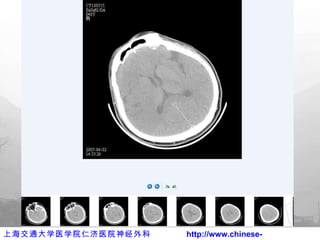

术后出院前 CT

术后 3D CT